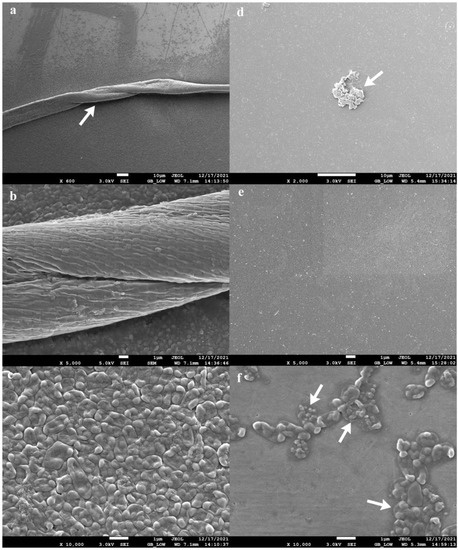

3.4. Anti-Biofilm Assay of Bacteriophage Cocktail on Urinary Catheters and Borosilicate Glass